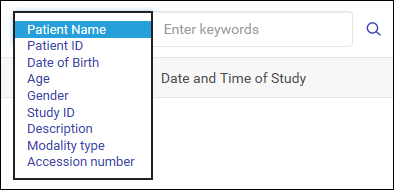

用户可以搜索患者以查找相关 DICOM 图像和相关信息。

搜索患者